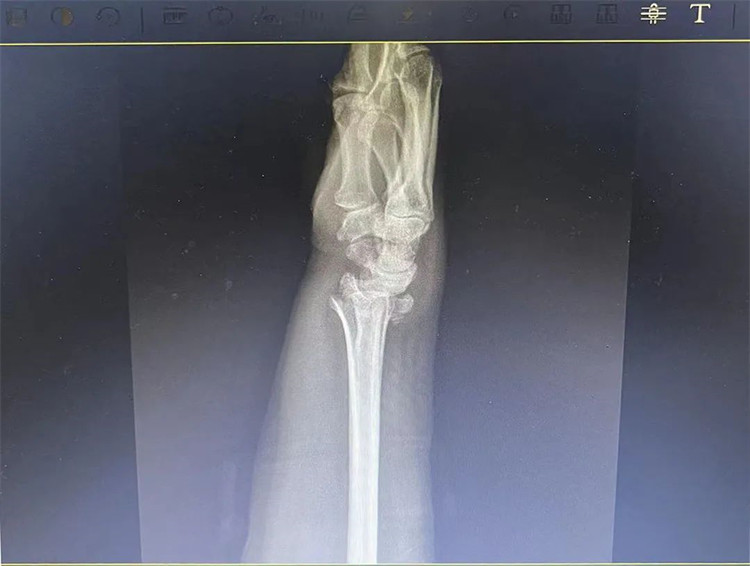

患者老年女性,50多歲,在騎電動(dòng)車停下時(shí)因電動(dòng)車倒下,右手著地,當(dāng)即感覺,右腕及骶尾部腫痛伴右關(guān)節(jié)畸形、活動(dòng)受限,急來我院就診。門診醫(yī)師結(jié)合病史、查體及輔助檢查后,診斷為:右橈尺骨遠(yuǎn)端骨折、骶尾部挫傷并收入住院部。